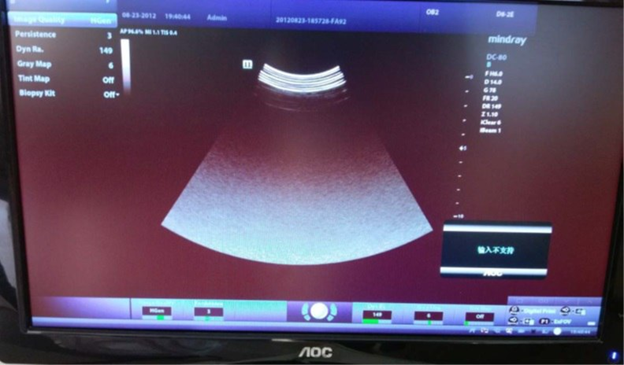

Отсутствие эхо-сигнала на датчиках

⚠️ Проблема: После включения питания на всех датчиках отсутствует эхо-сигнал, однако система определяет эти датчики. В меню системной информации и меню подробной информации о системе на экране ECN/TCN отображается «Incorrect», на плате Front-End Power Main Board отображается «???».

💡 Причина: Нам необходимо удостовериться, имеется ли сбой только на одном датчике или на всех датчиках. В этом случае можно идентифицировать все зонды, но нет эхо-сигнала. При прослушивании датчика на наличие характерного звука мы обнаружили, что он отсутствуют, это означает, что напряжение PHV некорректное. Возможны сбои в платах transmission board, Front-End Power Main Board. После проведения самотестирования, в отчете о тестировании появляется следующее сообщение:

Проверив меню «About» и «About detail», мы обнаружили, что на ECN/TCN отображается «Incorrect», а в идентификаторе основной платы внешнего источника питания отображается «???», основная плата внешнего источника питания не может быть идентифицирована. В соответствии с этой ситуацией, логика, загруженная на плату Front-End Power Main Board, может быть повреждена, и по этой причине плата не может быть идентифицирована. После замены платы Front-End Power Main Board неисправность все еще существует. При объединении ID канала считывания с платой Front-End Power Main Board информация об ID будет загружена на плату Digital Board, а затем на цифровую плату через последовательный порт для идентификации ID платы Front-End Power Main Board.

Если с последовательным портом на плате Digital Board возникла проблема, это также приведет к невозможности определения ID, а затем к тому, что плата front-end power board не сможет нормально работать. В то же время в отчете о самопроверке платы board также отображается сообщение «Проверка монитора не пройдена», поэтому на плате Digital Board, возможно, что-то не так.

✅ Решение: Замените плату Digital Board.